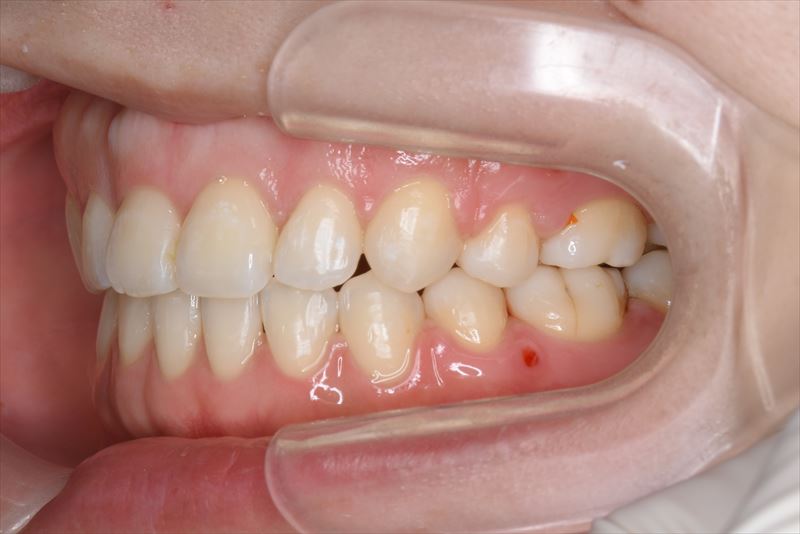

治療中

叢生、口唇の突出

上顎両側4番抜歯、下顎両側4番抜歯、下顎両側8番抜歯

臼歯のみの咬合、口唇の閉鎖が難しい状況でした。抜歯を行い前歯を牽引することで、良好な側貌と緊密な咬合を獲得できました。